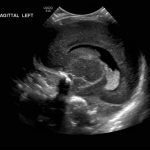

Age: 4 days (born at 24 weeks)

Sex: Male

Indication: Evaluate for germinal matrix hemorrhage

Grade 2 germinal matrix hemorrhage

Sample ReportLeft germinal matrix hemorrhage involving the caudothalamic groove and layering in the occipital horn of the left lateral ventricle without hydrocephalus (grade 2).

No abnormal brain parenchymal echogenicity or extra-axial collections.

Premature sulcation pattern.